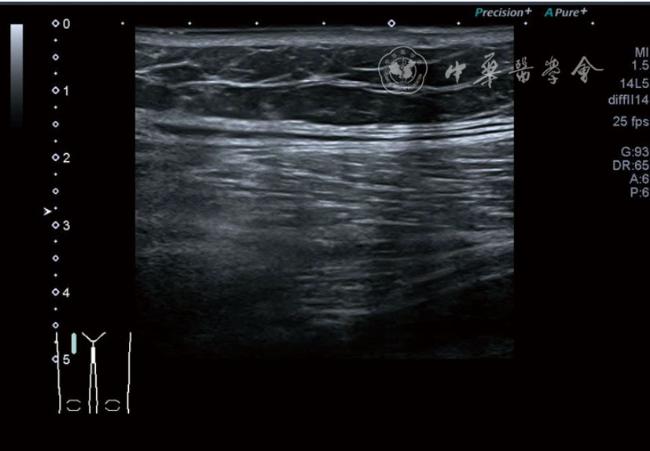

(五)超声影像学表现

患者采取侧卧位,患肢在上,屈膝20°。应用10~18 MHz高频线阵探头,扫查深度1~3 mm。长轴和短轴结合双侧对比扫查。超声影像学所见:短轴可见卡压腓总神经近端增粗,面积增大;长轴可见腓总神经卡压处变细,其近侧肿胀、回声减低,而在卡压远侧则表现正常(图35);一些受压严重者可以出现神经周围积液,卡压神经部位的筋膜增厚(图36);受压神经内血流增加对临床诊断意义更大(图37);探头在病变神经处加压常可引起神经刺激症状。腓总神经支配的肌肉有失神经支配改变,表现为肌肉回声增高和肌肉萎缩(图38)。